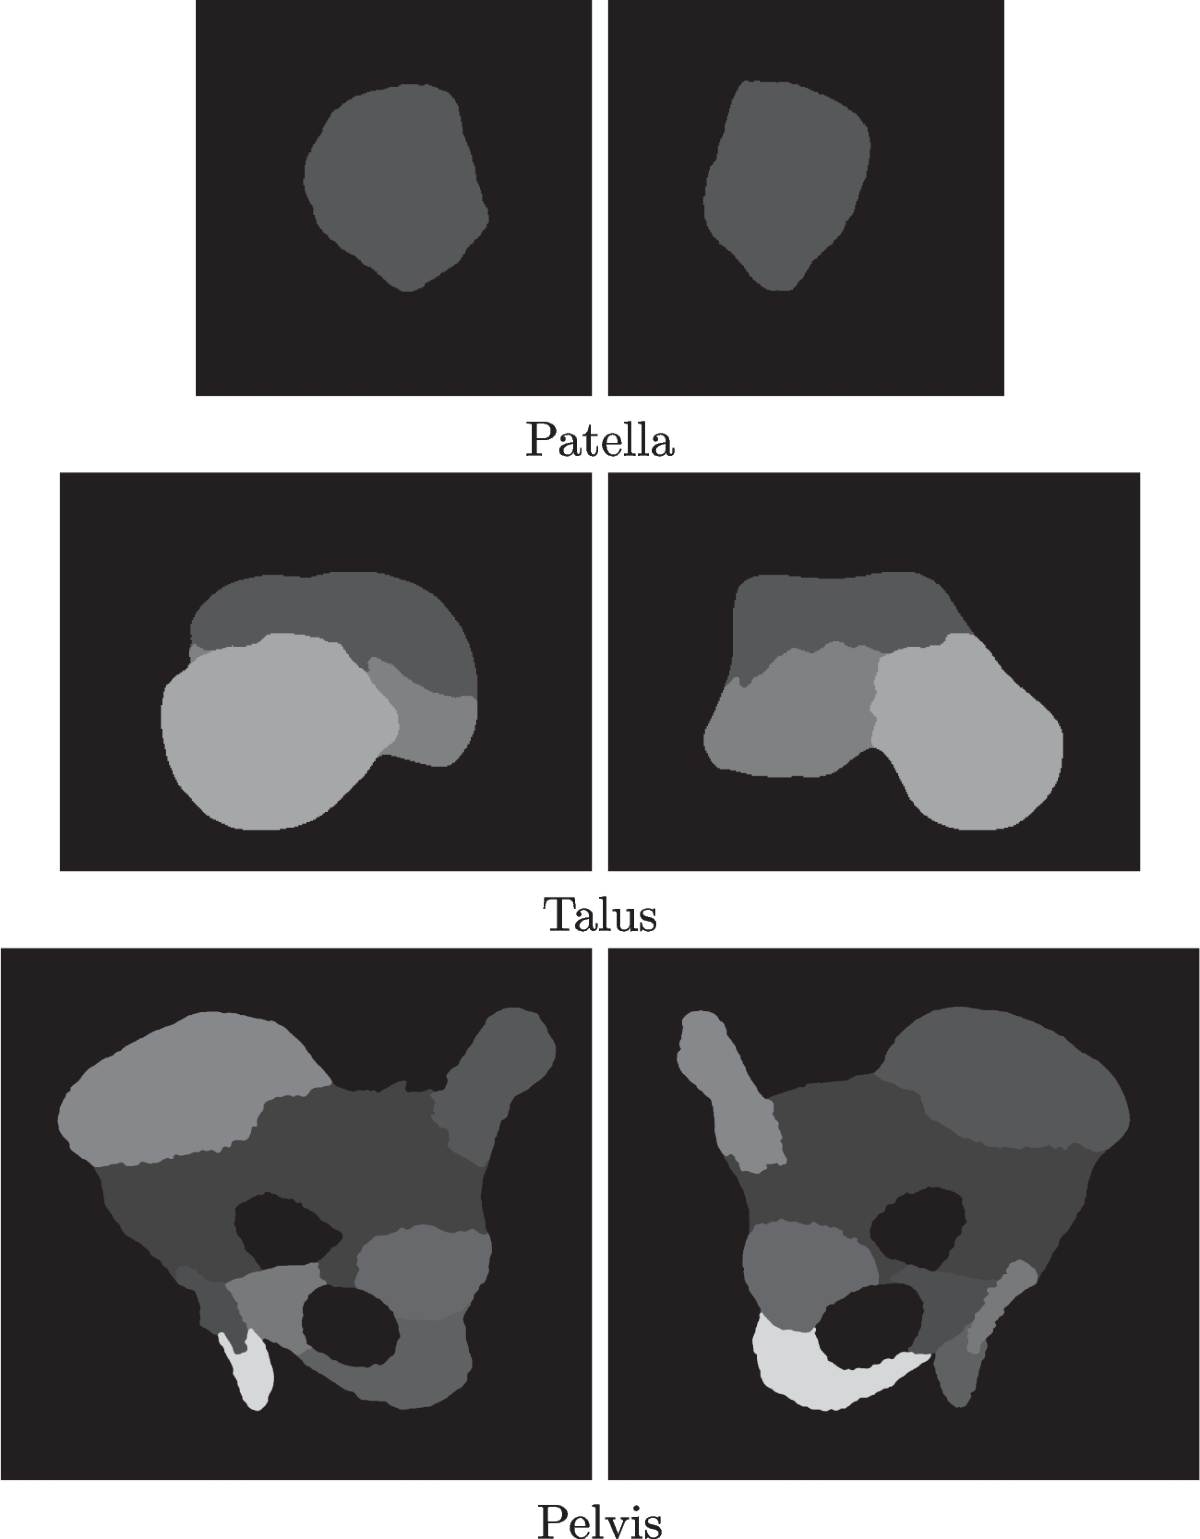

Talus robotics (92) 사진

Talus robotics funding (86) 사진